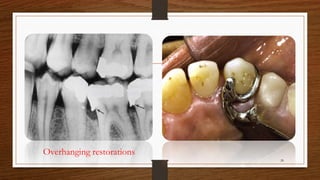

Overhanging restorations

28